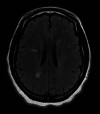

Viral infections can serve as a trigger for variable autoimmune, antibody-mediated demyelinating disorders. There is accumulating evidence that the severe acute respiratory syndrome coronavirus 2 (SARS-CoV-2) virus, causing coronavirus disease 2019 (COVID-19) infection and responsible for the current worldwide pandemic, can lead to a cascade of immune-mediated brain and spinal cord demyelinating injuries. However, such observation in the pediatric age group was only reported in very few patients. Thus, the heterogeneous spectrum of this phenomenon in children is still unfolding. We are reporting a case series of five pediatric patients with a variety of acute central nervous system (CNS) demyelinating disorders in the context of acute or recent COVID-19 infection. A 16-year-old female with anti-myelin oligodendrocyte glycoprotein (MOG) disorder, an eight-year-old male with acute disseminated encephalomyelitis (ADEM), a 13-year-old female with neuromyelitis optica spectrum disorder (NMOSD), and two 14 and 13-year-old females with new-onset multiple sclerosis (MS) are reported, all of whom presented acutely following COVID-19 infection. We propose that para and post-infectious CNS demyelinating disorders can potentially follow acute COVID-19 infection in children. Considering SARS-CoV-2 testing as a part of diagnostic workup is possibly useful. Awareness of the presence of this phenomenon can help in the recognition and management of those patients.